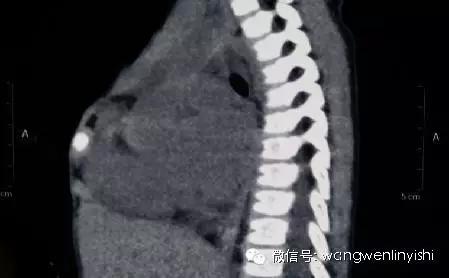

(裂开的中部深面为主动脉弓)

(下半胸骨连接部分仅2公分)

(侧外片显示,前胸壁结构明显破坏)